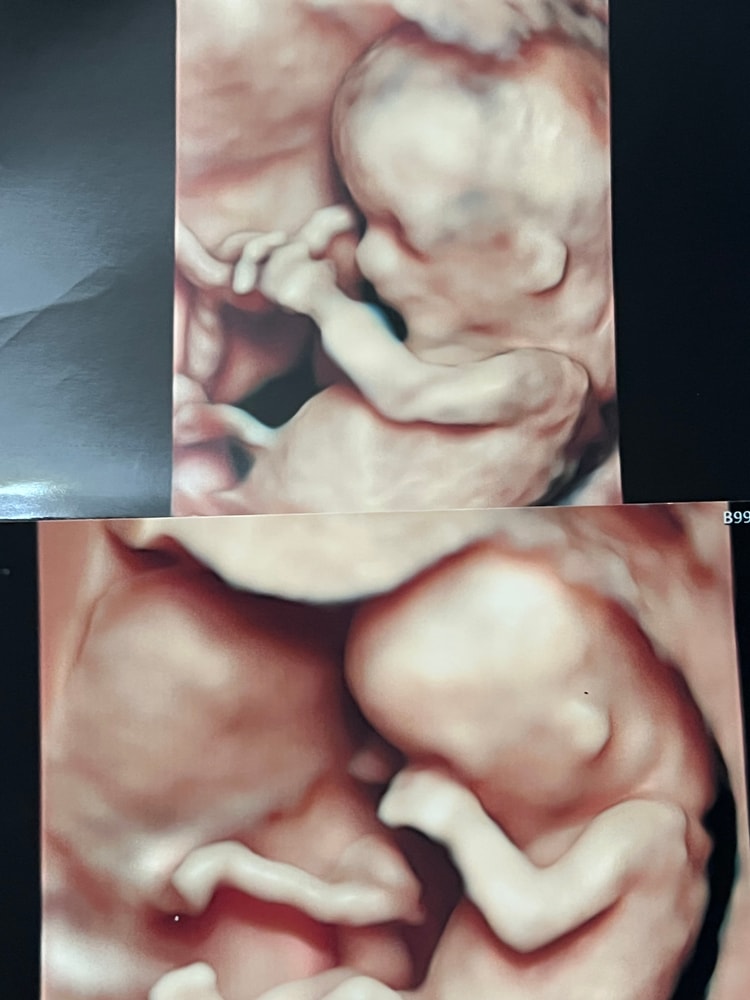

Странный вопрос задам 🌚, но на кого похож?

УЗИ, КТГ, доплерДевочка или мальчик?

Давайте без всяких « на таком сроке никто Вам не скажет » 🌚. Просто любопытно.

Похоже на мальчика)

Больше на мальчика похож. Я вот свои снимки разглядываю и тоже кажется внешне мальчик)